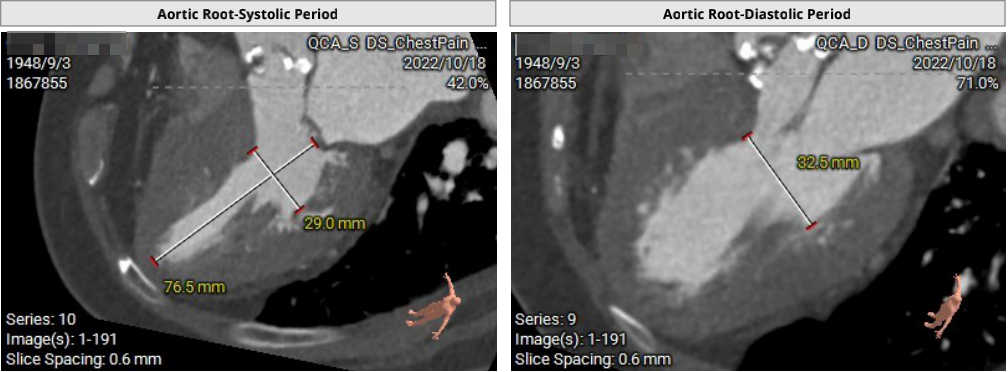

主动脉根部CTA

瓣环周长67.3mm,平均径21.4mm,LVOT周长73.0mm,平均径23.2mm;横位心76°,瓣叶交界钙化粘连;股动脉入路迂曲,分叉高度可,髂总-腹主钙化斑块;左侧血管平均最小内径6.0mm, 右侧血管平均最小内径6.1mm;左、右冠开口高度低,瓣叶长,窦宽相对瓣膜小,冠脉风险高。